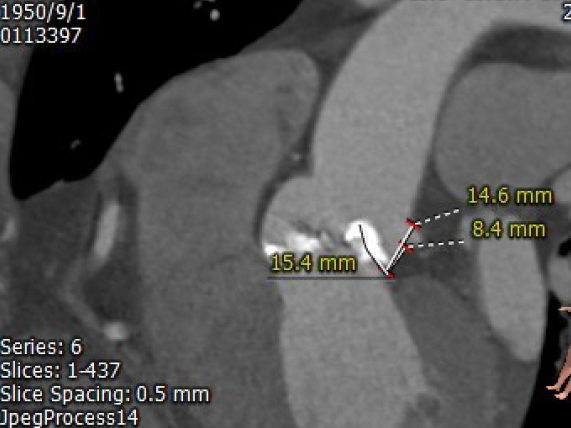

左瓣叶长度:15.4mm

右瓣叶长度:15.1mm

左冠开口高度:16.1mm

右冠开口高度:16.1mm